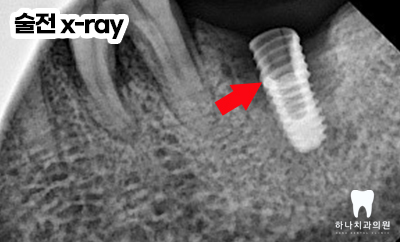

정밀 x-ray 촬영 결과, 기존에 식립되어 있던

인공치근의 파절선을 뚜렷하게 관찰할 수 있었고

앞쪽의 첫 번째 어금니 역시 파절과 뿌리 주변의

심한 골소실을 관찰하여

당일 발치 및 기존 임플란트 제거 후

울산삼산동치과에서 임플란트 식립을 계획하게 되었습니다.